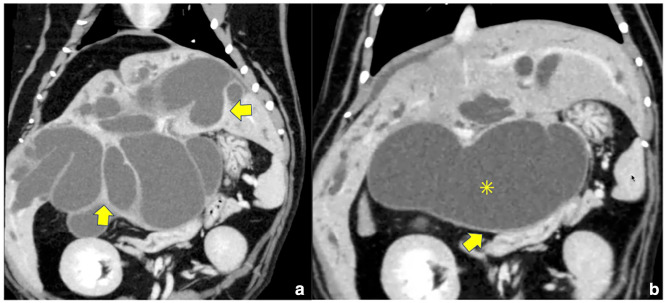

Case summary: An 8-year-old castrated male mixed-breed cat was presented with recurrent vomiting, weight loss and abdominal distension. Blood work revealed hyperbilirubinaemia and elevated liver enzyme activities. Abdominal ultrasound and CT showed marked dilation and obstruction of the common bile duct (CBD) due to chronic cholecystitis and cholangiohepatitis. The cat was diagnosed with CBD obstruction secondary to chronic cholecystitis and cholangiohepatitis and was initially treated with antibiotics and prednisolone. Surgical intervention was performed because of complete CBD obstruction and worsening icterus that was unresponsive to medical management. A choledochoduodenostomy was performed using a simple side-to-side anastomosis between the CBD and the duodenum. The patient recovered uneventfully after surgery without significant complications. At the last follow-up, 6 months postoperatively, the cat remained clinically stable.